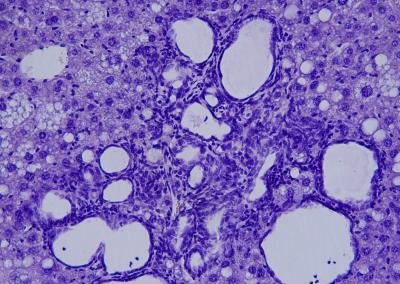

image: A cholangiocarcinoma under the microscope.

Researchers at the Centro Nacional de Investigaciones Cardiovasculares (CNIC) have discovered a mechanism controlling the development of a type of liver cancer. This study, published today in the Proceedings of the National Academy of Sciences (PNAS), partly funded by the Spanish Association Against Cancer, has identified a protein that, when blocked, dramatically reduces the impact and progression of this type of cancer, called cholangiocarcinoma. This work has been possible because CNIC researchers have developed an animal model where alterations in the production of bile acids have been proved to cause this type of tumor.

Liver cancer is the fifth most frequent cancer and the second main cause of cancer-related deaths worldwide. Cholangiocarcinoma, the second most common liver cancer, starts in the bile ducts and has a clinically symptomless progression. Because there are no early markers, most patients are diagnosed at an advanced stage and die due to the spread of cancer or metastasis.

Researcher Elisa Manieri explained that, over time, this accumulation of bile acids has a "toxic effect" on the liver. Bile ducts begin to proliferate excessively, triggering the formation of multiple cholangiocarcinomas with clinical markers, which are remarkably similar to those of patients with this type of cancer. In fact, "it is the first time that we have found the increase of a cholangiocarcinoma patient marker in mice models." This indicates that these mice could offer new clues to assess novel cholangiocarcinoma therapies.